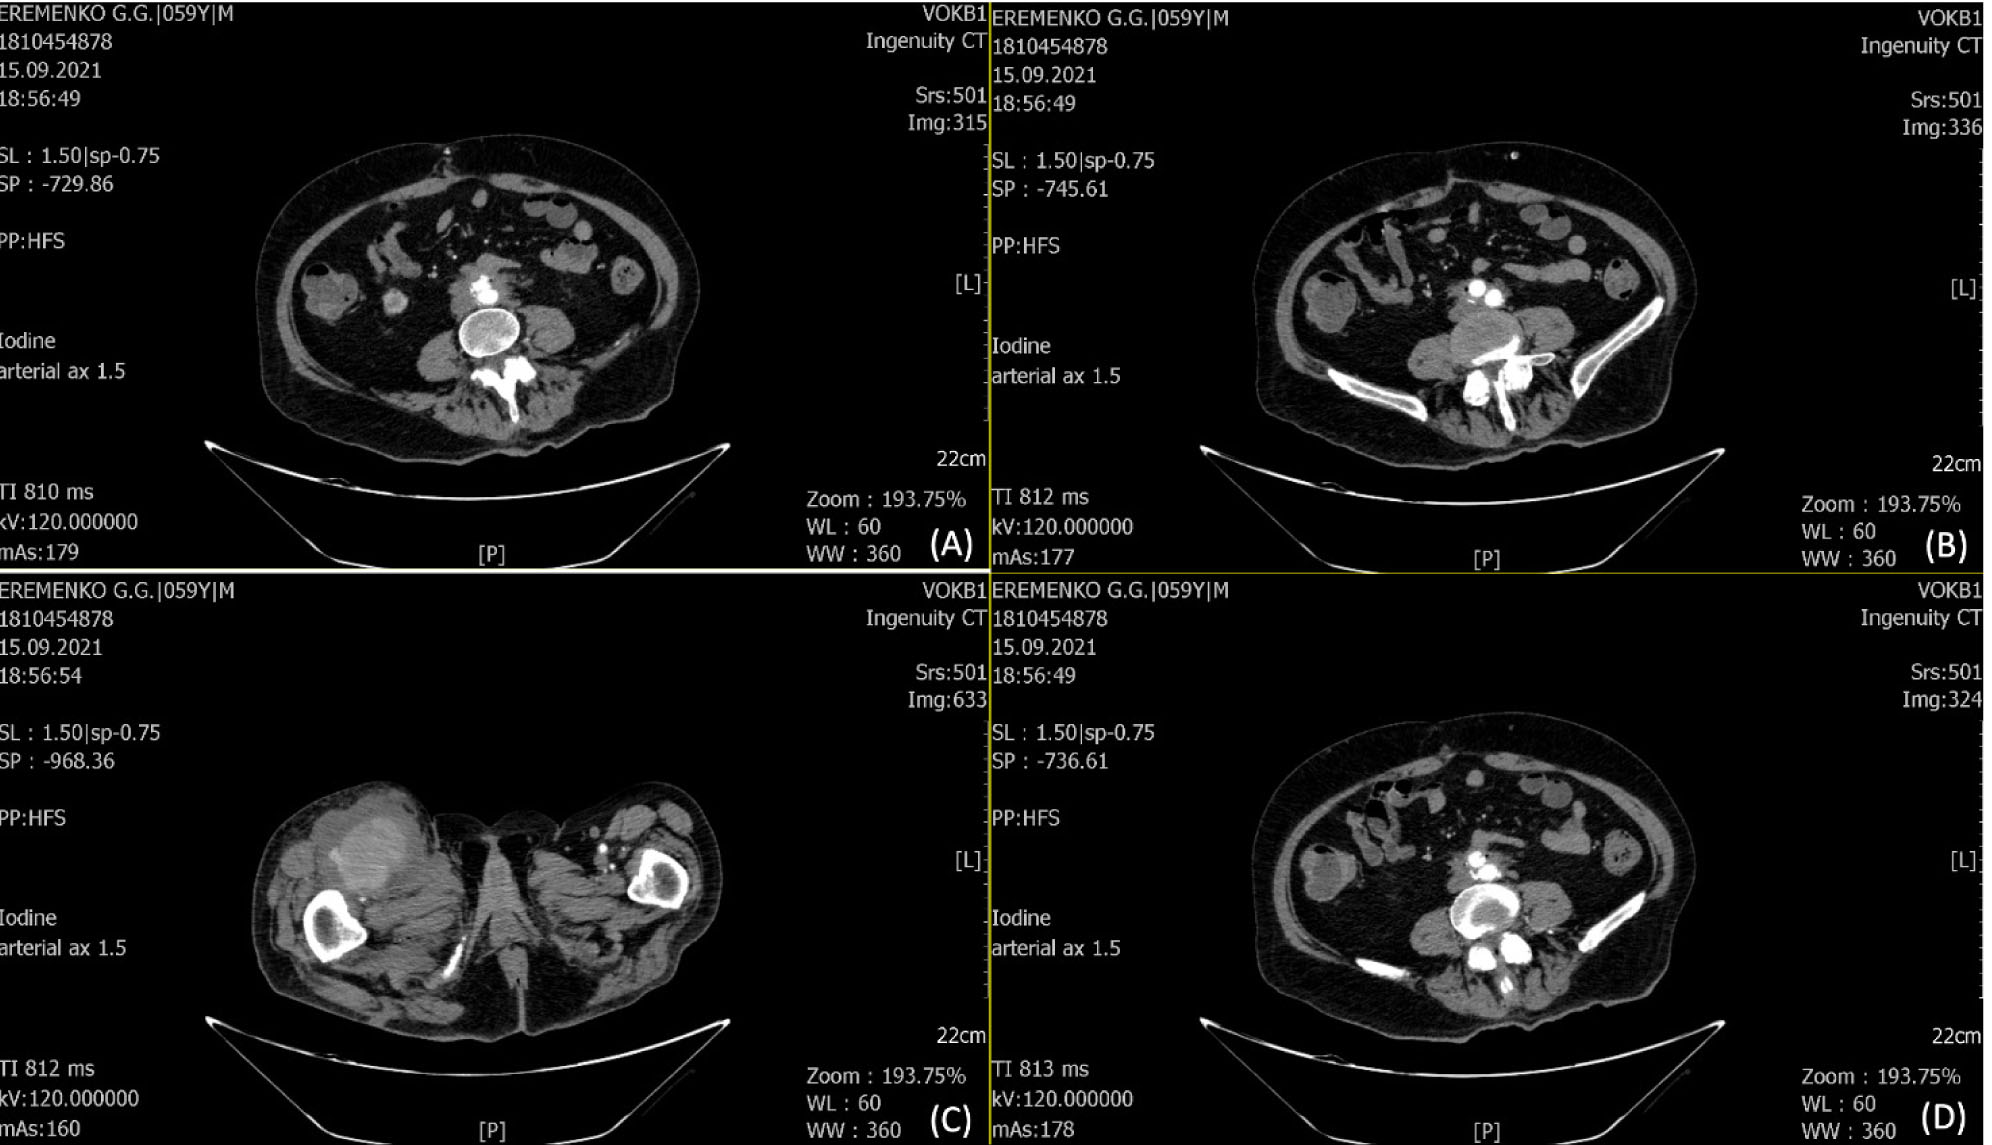

Пациент 62 лет поступил в ГБУЗ ВОКБ № 1 20.12.2022 г. в тяжелом состоянии, с жалобами на отек, распирающие боли в правой нижней конечности, периодические приступы повышения АД, температуры тела, одышку, общую слабость. В анамнезе от октября 2021 г. находился на стационарном лечении в хирургическом отделении ГБУЗ ВОКБ № 1 с подозрением на рецидивирующее ЖКК, при обследовании на ФГДС язв не обнаружено. При КТ брюшной полости с контрастированием выявлена аневризма брюшного отдела аорты с интимным прилеганием к стенке двенадцатиперстной кишки с подозрением на формирование свища (пузырьки воздуха в тромбомассах полости аневризмы). 10.11.2021 г. по решению консилиума проведено оперативное вмешательство: резекция аневризмы брюшного отдела аорты с аорто-подвоздошно-бифуркационным внутримешковым протезированием, ушивание дефекта стенки двенадцатиперстной кишки, наложение холецистостомы. Послеоперационный период без осложнений, дренаж из брюшной полости удален на 15-е сутки, пациент выписан в удовлетворительном состоянии. С начала октября 2022 г. стал отмечать боли в правом бедре, затем отметил уплотнение и чувство жара в бедре, боли усилились. 03.10.2022 г. обращение в приемный покой ГБУЗ ВОКБ № 1, выявлена и вскрыта флегмона правого бедра от 03.10.2022 г., с положительной динамикой пациент выписан для дальнейшего лечения по месту жительства. С начала декабря стал отмечать отек, распирающие боли в правой нижней конечности, периодическое повышение температуры тела. Операция: 21.12.2022 г. вскрытие абсцесса задней поверхности правого бедра. На УЗИ мягких тканей правой голени выявлено наличие свободного жидкостного компонента, в срочном порядке 23.12.2022 г. выполнено вскрытие флегмоны правой голени, санировано до 100 мл гнойного отделяемого. 26.12.2022 г. получен результат бак посева – E.coli 10 × 8, чувствительная к меропенему. По КТ брюшной полости и органов малого таза с контрастированием от 26.12.2022 г. – МСКТ картина локального расширения инфраренального отдела аорты. Отмечаются отдельные увеличенные параортальные лимфатические узлы. Воспалительные изменения в мягких тканях бедра (множественные абсцессы) (рис. 3).

Рис 3. КТ с контрастированием. 1, 2 – единичные пузырьки воздуха в парапротезной области; 3 – воспалительные изменения в мягких тканях бедра в зоне сканирования